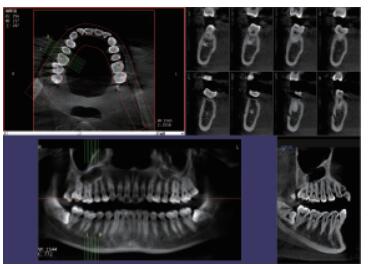

口腔CBCT 三維重建任意斷層

三維重建任意斷層

專有三維重建算法,可提供任意位置高清斷層影像。

口腔CBCT 多平面組合重建

多平面組合重建

可同時觀察軸向面、冠狀面和矢狀面圖像,方便臨床診斷。